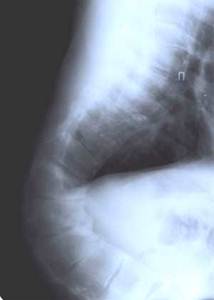

Больной Сав-ко 15 лет. Кифотическая деформация. До операции

После операции